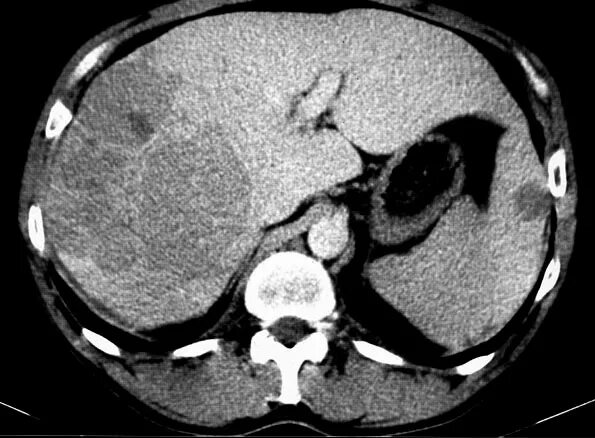

Цирроз печени кт